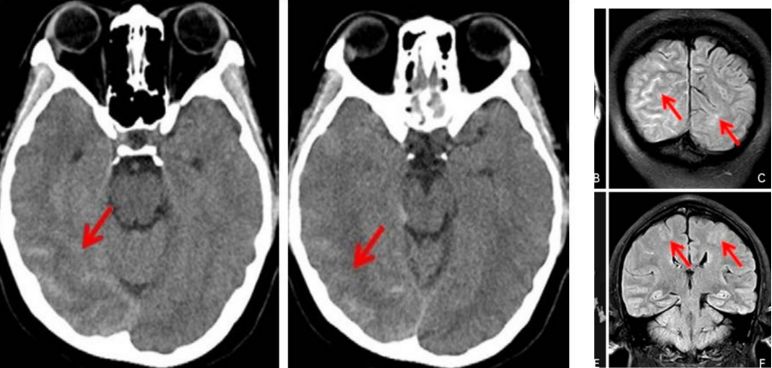

蛛网膜下腔出血的基础诊断

蛛网膜下腔出血的基础诊断,原来这么容易!

一例蛛网膜下腔出血患者的头CT,你能读出哪些信息?】-中华医学网

蛛网膜下腔出血的脑部CT图

答:蛛网膜下腔其实分布范围挺大的,大脑表面都是,还有一些在大脑底下的脑池内也算,所以回答你出血的具体部位不好说的。而且蛛网膜下腔出血,如果是血分布的局限,那就考虑就